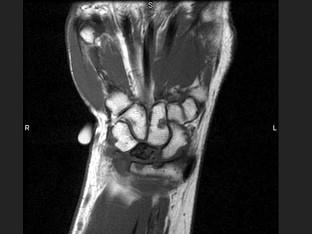

问题 女,41岁,纺织工,腕部疼痛无力数周,结合CR和MR,最可能的诊断是?(?)

选项 A.月骨结核 B.月骨缺血坏死 C.骨质疏松 D.骨髓炎 E.骨软骨炎

答案 B